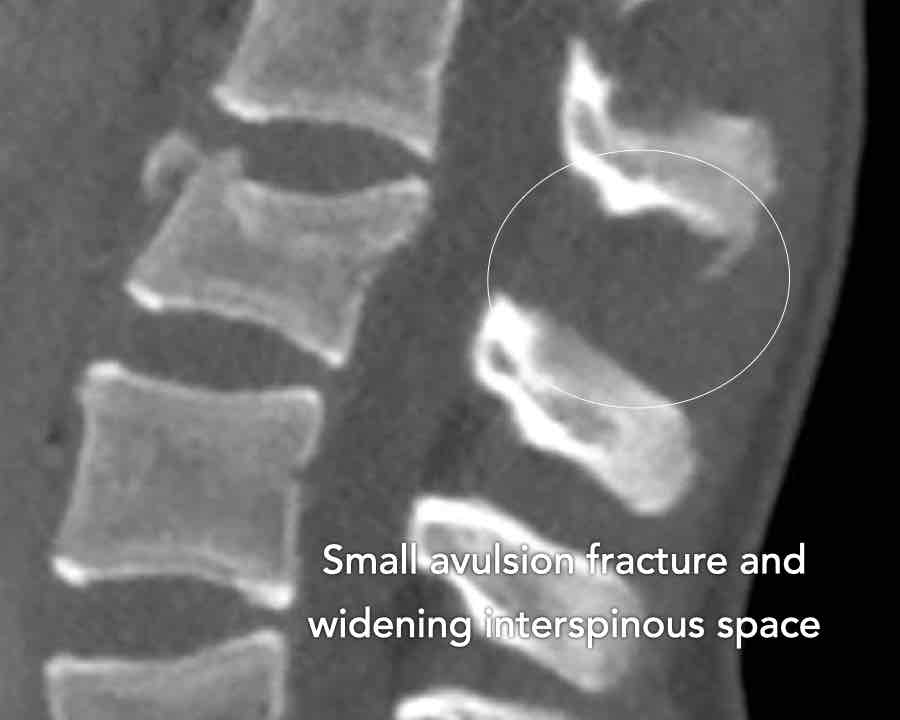

Findings

- Clear widening of the interspinous distance (yellow arrow)

- Black arrowhead: small avulsion fracture to the flexion distraction

- MRI better depicts the ligamentous injury, which was suspected on CT

Conclusion

Injury type B2

- Subtle widening of the interspinous distance (white circle)

- Small avulsion fracture spinous process (yellow arrow)

- Compression fracture with involvement of one endplate and posterior wall (1+2 points)

Injury type B2 + A3